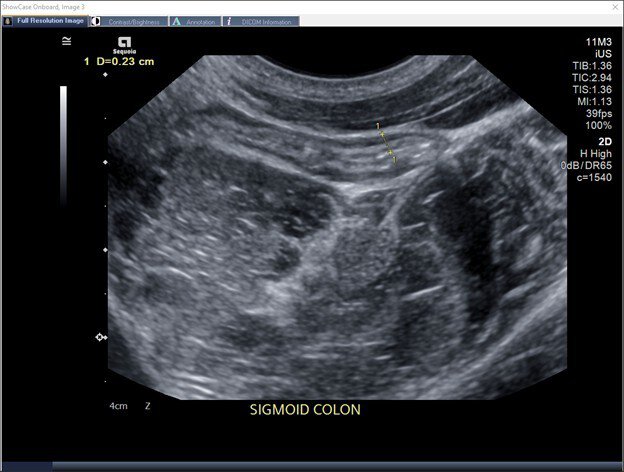

Normal appearing sigmoid colon with normal bowel wall thickness on IUS

IUS allows visibility of the large intestine (colon) and the small intestine (the terminal ileum) where disease activity can be assessed using several markers such as bowel wall thickness, hyperemia (increased blood flow), and disruption of wall layers.

"With IUS, I'm able to see how thick the bowel wall is and if there is an increased blood flow to that area, which would indicate inflammation," explains Dr. Suppa. "I can also see if there is any disruption to the layers of the bowel wall or signs of complications such as strictures." This allows him to determine how well a patient is responding to a prescribed treatment without the lag time of lab results or the need to schedule other procedures or imaging.